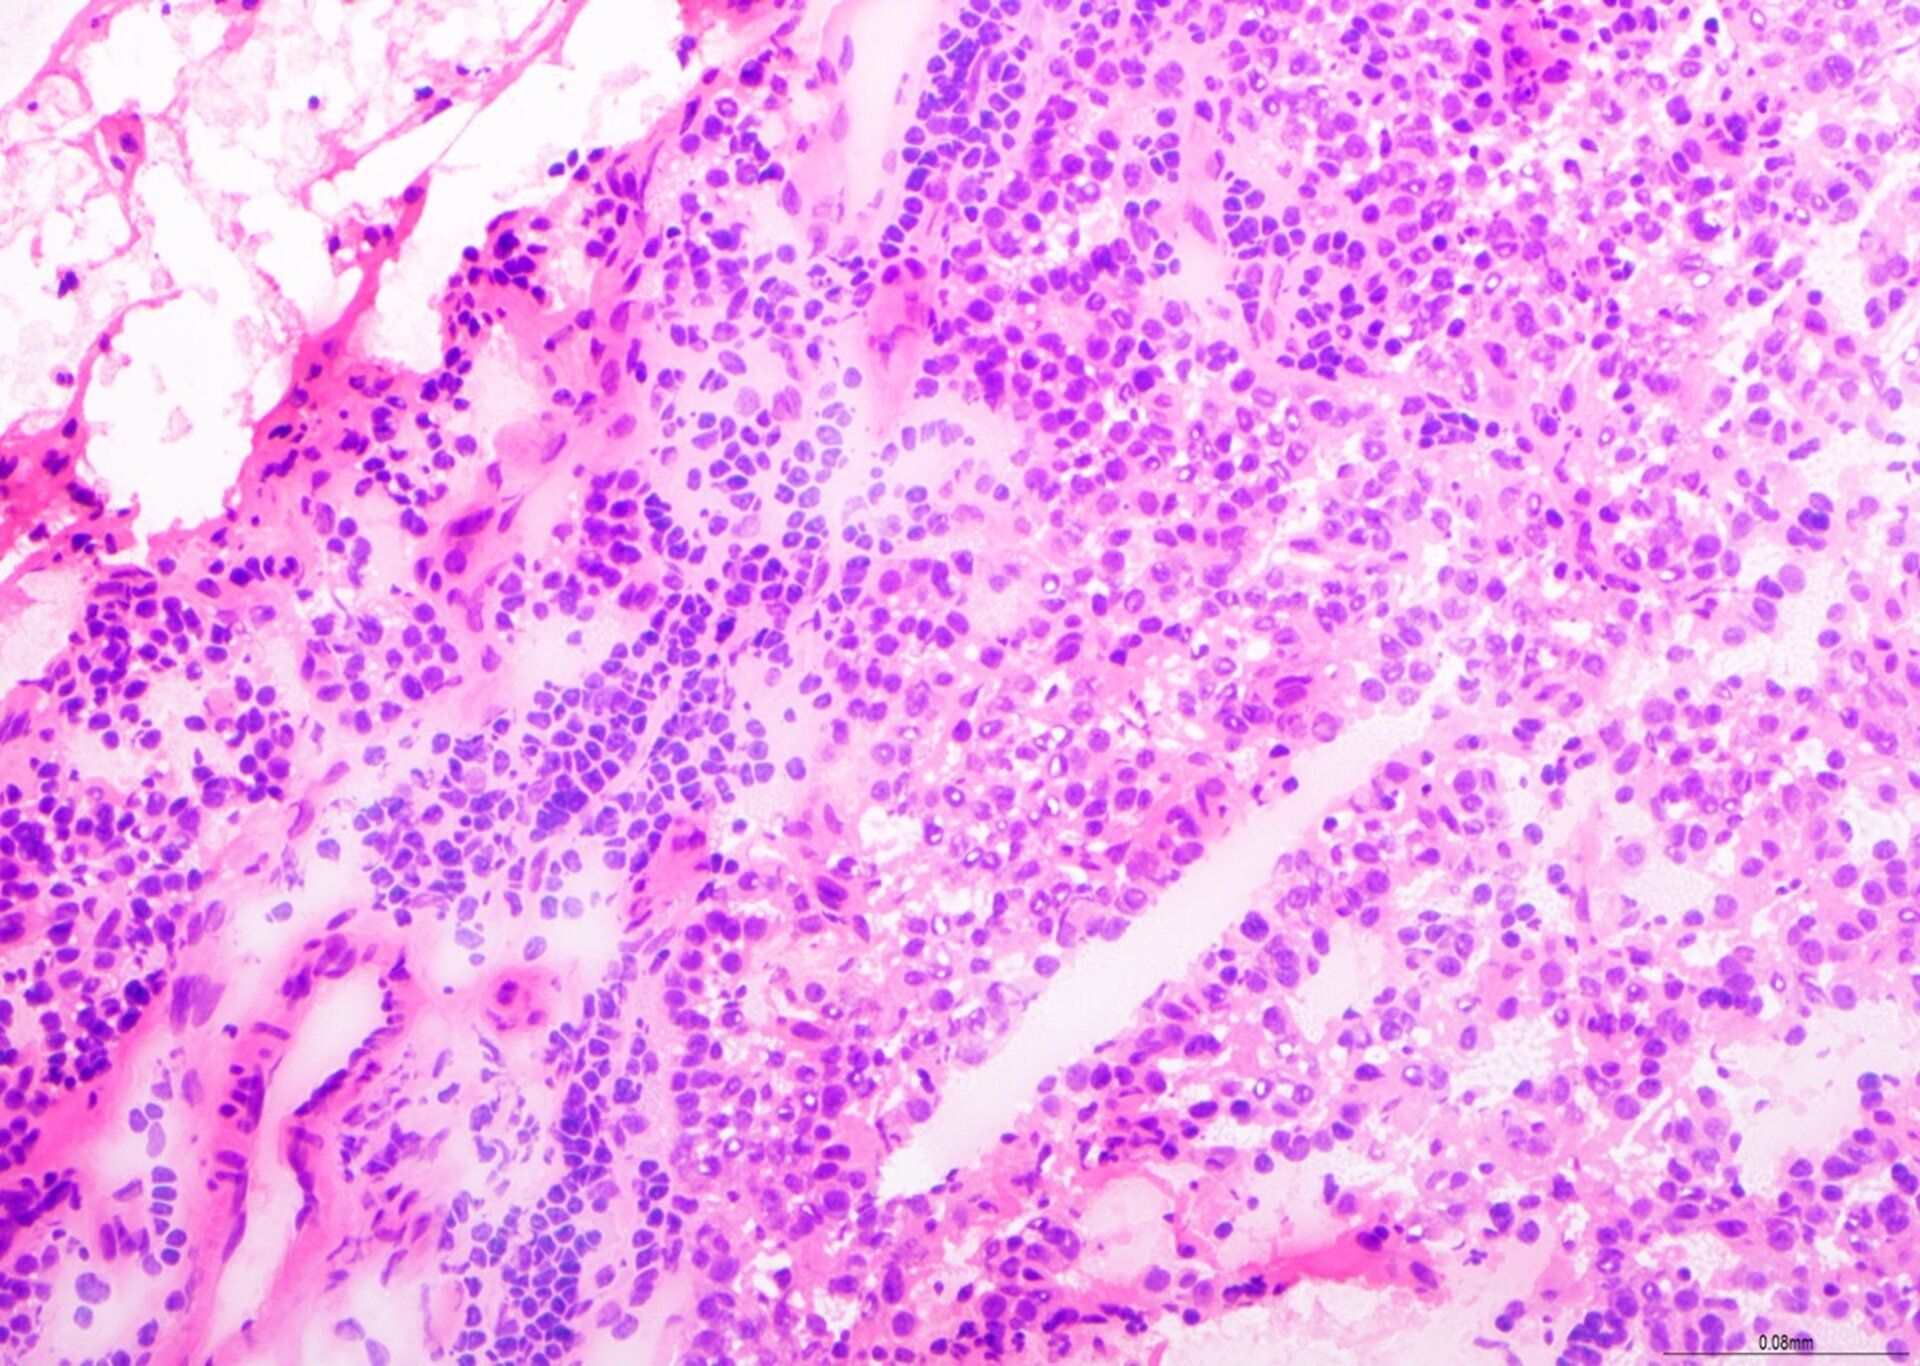

H&E - BMT-skema

Dit is 'n uitstekende voorbereiding vir 'n BMT-biopsie, met gebalanseerde H&E-kleuring, goeie chromatiendetail en selektiewe kleuring van seltipes binne die beenmurgweefsel. Hierdie skyfie is 9/10 tydens assessering behaal.